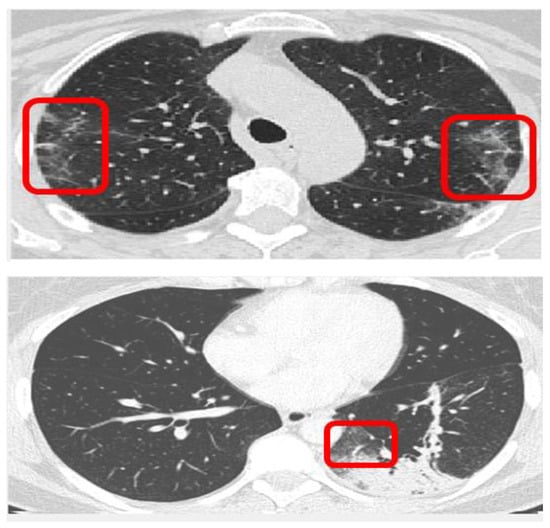

To generate the most effective training results, the input data was pre-processed with various methods [20]. The approach involved converting grayscale input images into binary images using fuzzy logic to isolate ground-glass opacity sections. Grayscale conversion to binary images presented a variation of results. To extract meaningful features from the training set, fuzzy logic edge detection was used on a binary image that was created from a grayscale image filter using adaptive thresholding. Figure 2 shows a COVID scan in binary format. The aim was to analyze the GGO and consolidation areas to form a distinct differentiation between COVID and non-COVID scans. The consensus is that COVID scans display patterns of white pixels (1′s) in binary form, whereas non-COVID scans will display minimal white pixels or none. Figure 3 shows inverted versions of the source image where the black pixels are the isolated consolidation sections [21]. Figure 4 is an example of a COVID image that is filtered to display the most important parts of the image. The white patches on the edges are the detections of GGO presence. By using the grayscale thresholding function, the values were calculated within the range ‘i’ as shown by the expression (95 < i < 145).

In Figure 3, the series of images being shown are the different output resolutions of the feature map to be used by the neural network. The top images are COVID scans and the bottom images are non-COVID scans. The approach used was to model a neural network classifier as the final layer of the CNN. The accuracies of the classifications were used as performance metrics for the most input image resolution as shown in Table 1, where both SVM (Support Vector Machine) and KNN (K-nearest neighbors) classifiers were used. To improve the classification accuracy, different feature extraction methods were used and evaluated. The feature extractors used were SURF (Speeded-Up-Robust-Features), MSER (Maximally Stable Extremal Regions), Bag of features and Haar Wavelet Transform.

Figure 2. Region analysis of thresholding image as a binary file (positive COVID scan).

Figure 3. Different resolutions of the pre-processed images by using multi-level thresholding.